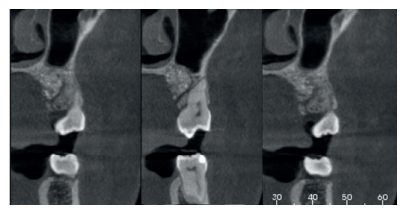

Caso clínico: se presenta un caso clínico de una mujer de 20 años, sin antecedentes médico-quirúrgicos de interés, que acudió a consulta remitida por su ortodoncista, para la extracción de un premolar maxilar retenido, en posición invertida. Tras la extracción del premolar y del tercer molar inferior retenidos, se obtuvo dentina procedente de ambos, para la regeneración ósea guiada del defecto resultante de la extracción del premolar, realizando revisiones a la semana y a los 4 meses de la intervención.

Clinical case: a clinical case of a 20-year-old woman is presented, with no interesting medical record, who went to dental clinic for removal of an inverse maxillary bicuspid retained. After maxillary bicuspid and lower third molar extractions, autogenous dentin was obtained from both teeth, to perform a guided bone regeneration of the bicuspid defect. A week and 4-month check-up were carried out.

El objetivo de este caso clínico es presentar la eficacia de la dentina autógena como material de injerto en un procedimiento de ROG, tras la exodoncia de un premolar superior izquierdo retenido, en posición invertida.